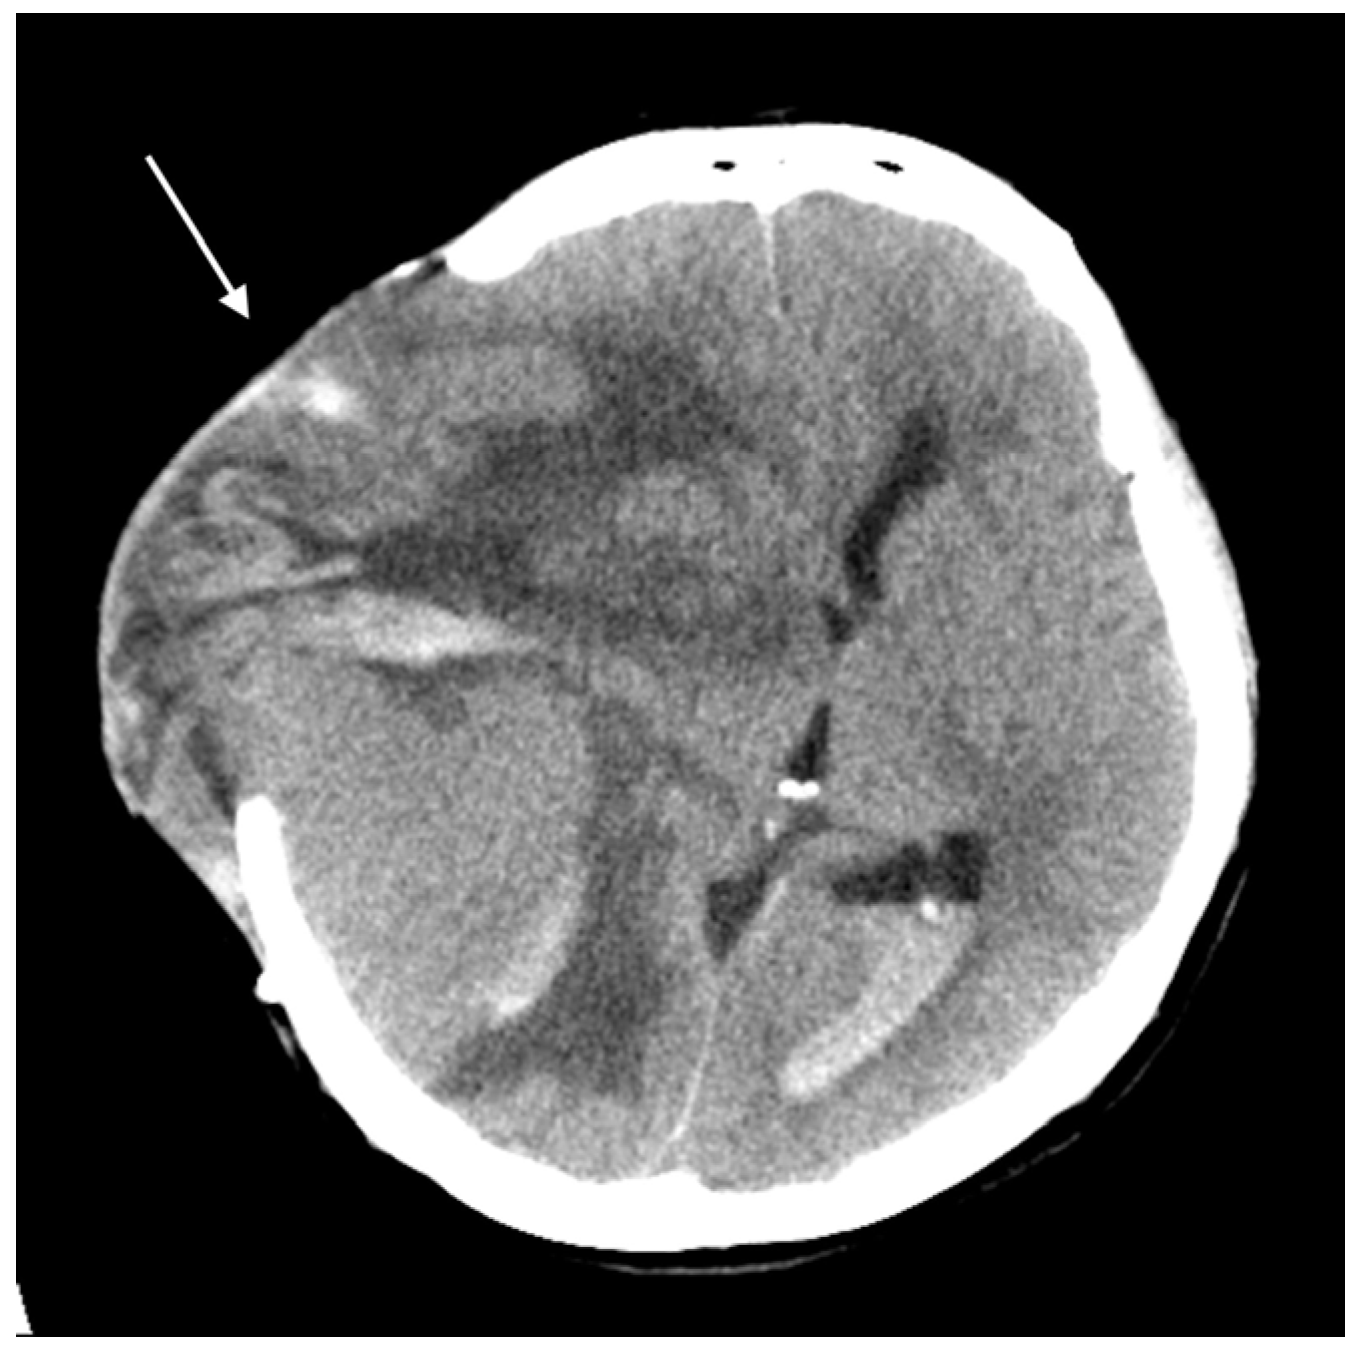

2. Detailed Case Description